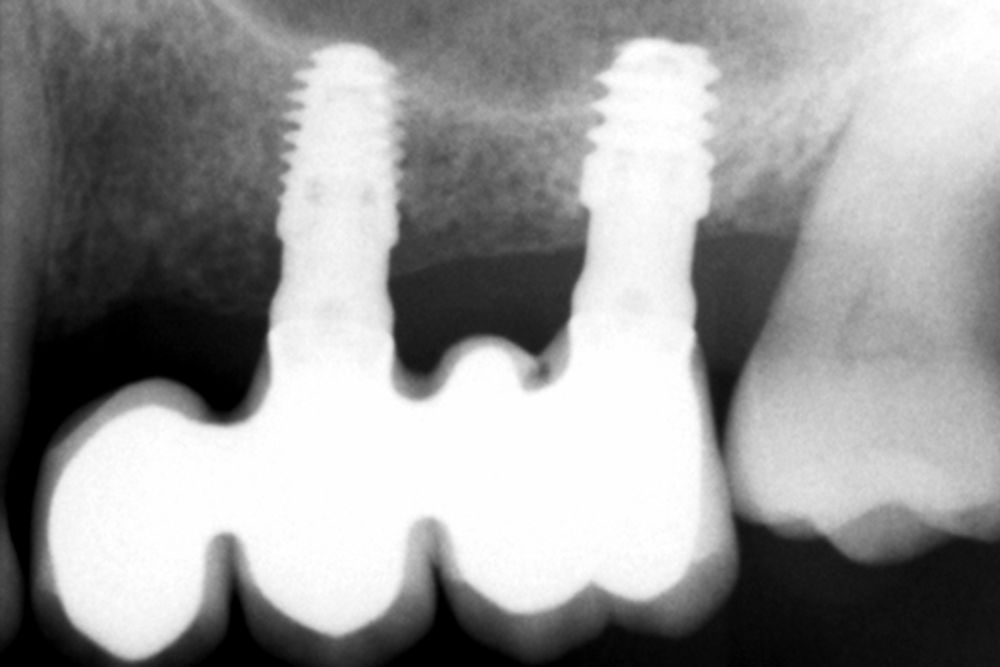

Una vez colocados los implantes, podemos realizar incluso carga inmediata, ya que, aun en condiciones de baja densidad y escasa altura ósea residual, con el protocolo anteriormente descrito se logra la estabilidad primaria suficiente (Figuras 25 y 26). Elaboramos una prótesis de carga inmediata atornillada sobre transepitelial (colocados en el momento de la cirugía y mantenidos posteriormente para no romper el hermetismo), confeccionada en resina con una estructura de barras articuladas. Esta prótesis nos proporciona carga progresiva mientras se produce la integración de los implantes, lo que favorece este proceso y permite reconstruir el patrón oclusal perdido, dado que presenta múltiples ausencias dentales del sector posterior maxilar. La carga progresiva en los implantes dentales es una técnica que permite una transición gradual de fuerzas sobre el implante, favoreciendo la adaptación biológica y la estabilidad ósea a lo largo del tiempo. En lugar de aplicar una carga inmediata completa, se introduce una presión controlada y creciente durante el periodo de cicatrización, lo que facilita una mejor osteointegración y reduce el riesgo de sobrecarga temprana. Este enfoque es especialmente útil en casos donde la calidad ósea es comprometida o cuando se busca una mayor predictibilidad en el tratamiento12.

Transcurridos 6 meses desde la carga inicial progresiva, se puede elaborar la prótesis definitiva, trasladando los parámetros de la prótesis provisional (Figura 27). La paciente continúa en seguimiento durante un año, realizándose radiografías de control para el monitoreo del hueso crestal, sin encontrarse pérdida ósea asociada en ninguno de los implantes (Figuras 28-29).